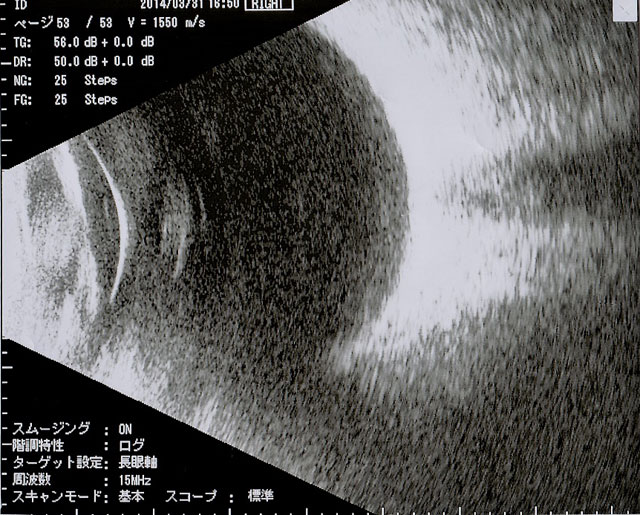

眼球内の病変を超音波で描出します。白内障や眼底出血で眼の中が見えない時でも、眼の中の状態がある程度わかります。